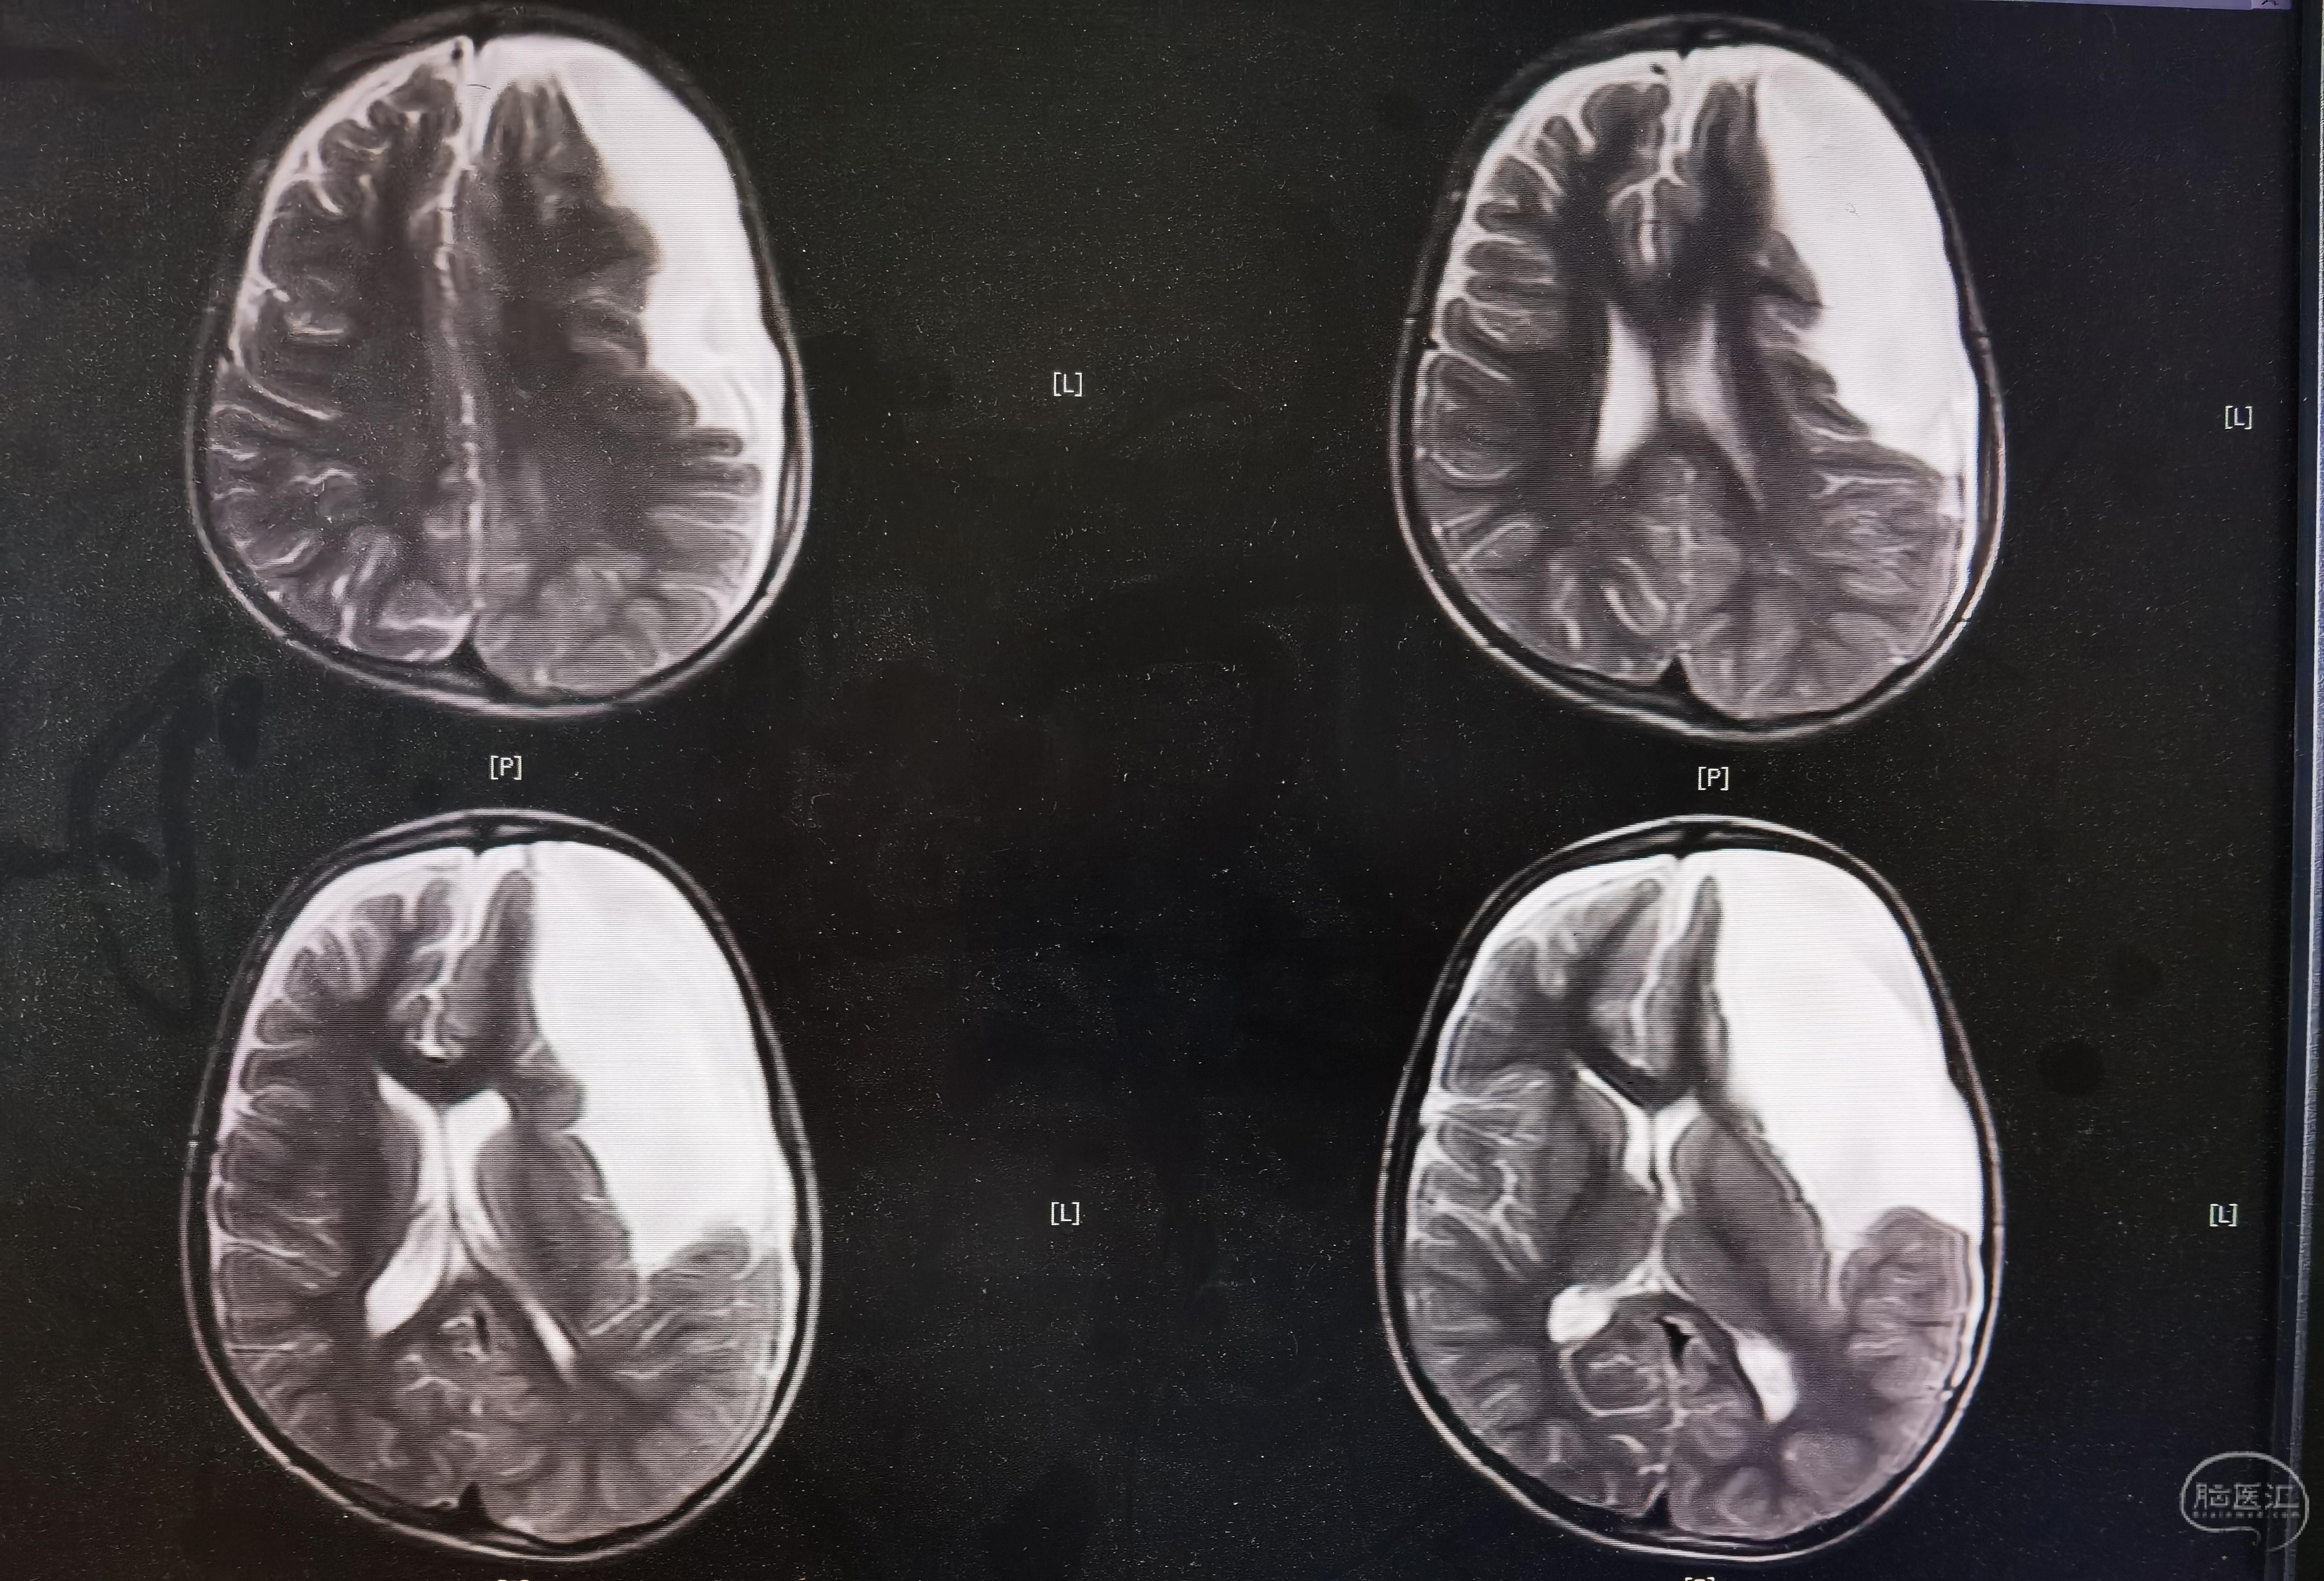

8岁男孩,以“头部外伤后头晕8天”入院,患儿8天前于3米高处坠落摔伤头部,伤后有昏迷史,当地医院CT提示左额颞巨大蛛网膜囊肿,破裂可能。患儿伤后感头晕,当地医院建议转至我院。我院完善头颅MR提示左额颞巨大蛛网膜囊肿,局部越过中线突入右侧镰旁挤压右额叶,左侧额颞岛叶明显受压,囊肿破裂可能。

术前MR